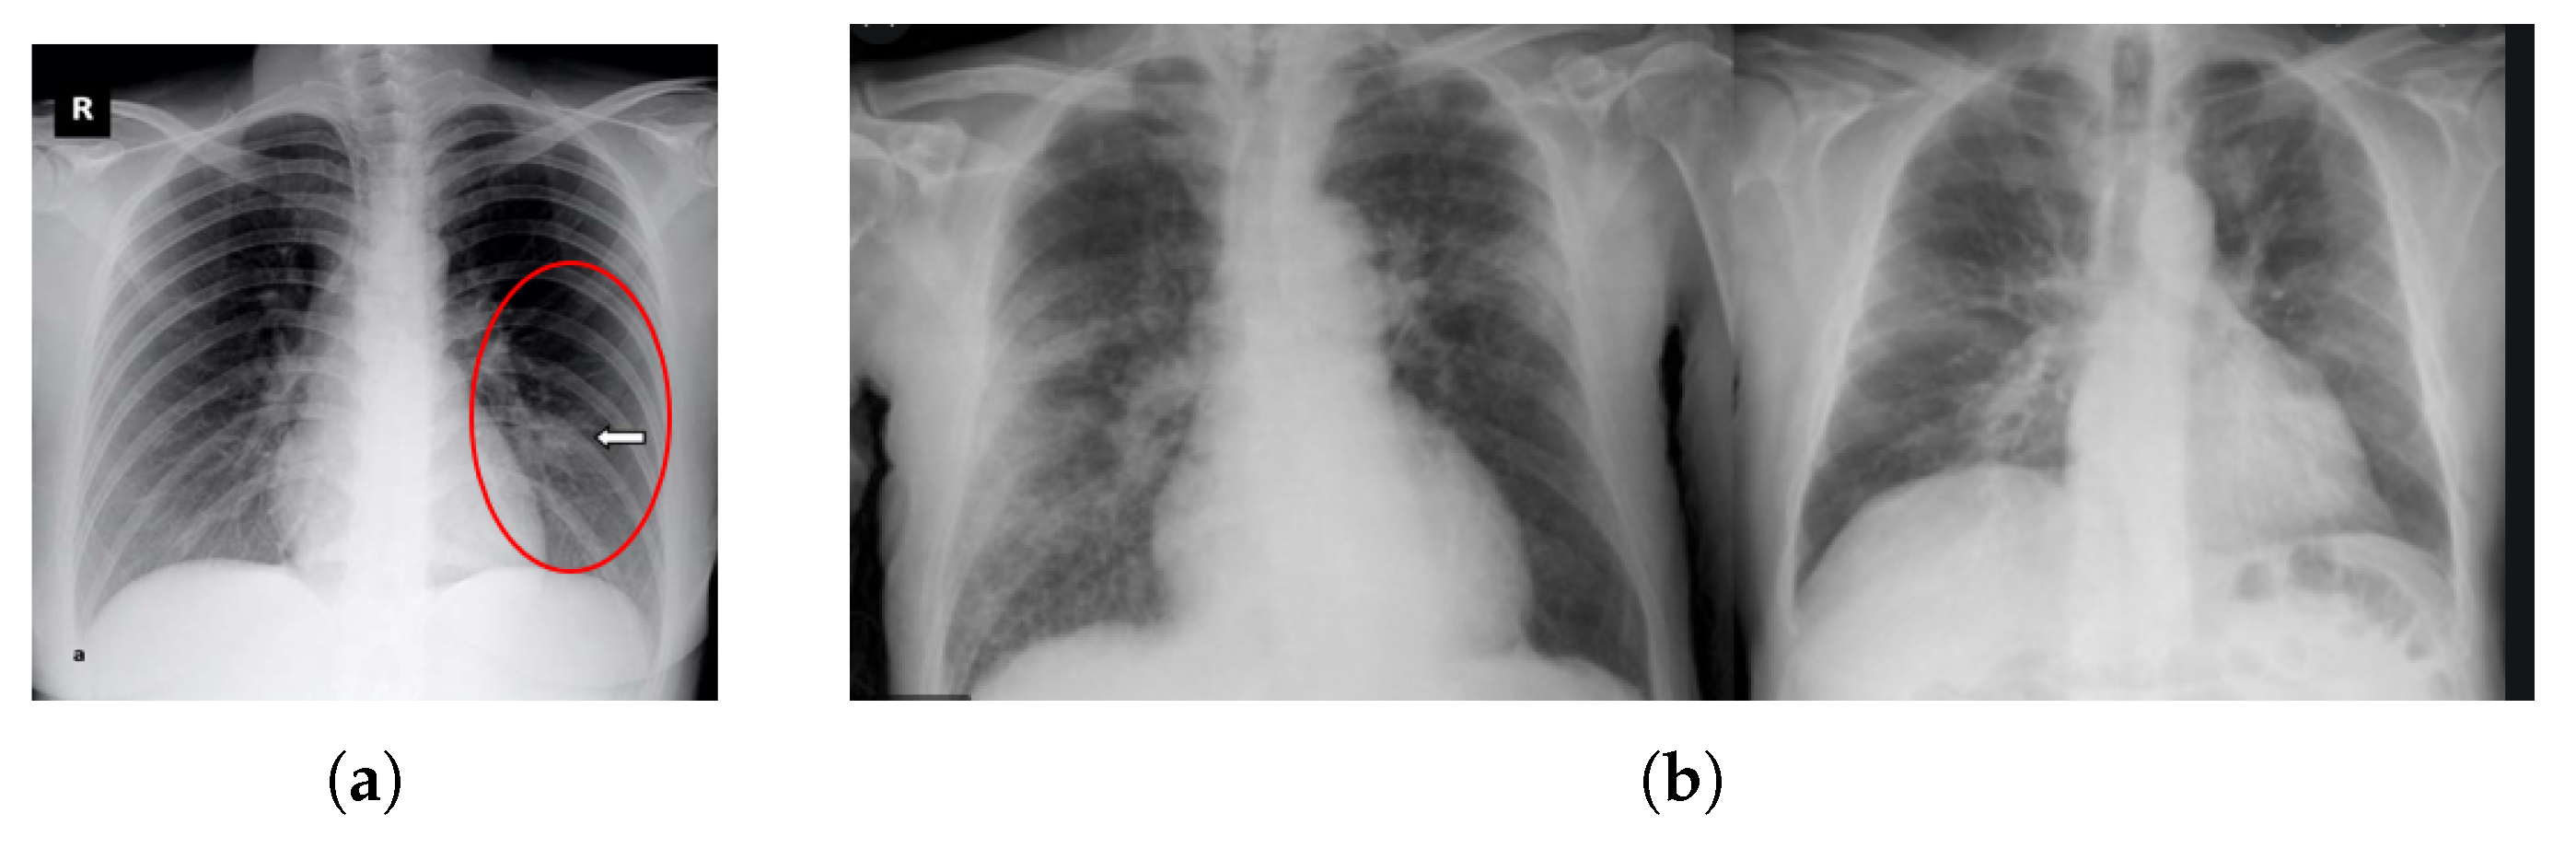

Research has found some variations in X-rays and CT scan images of a patient before the onset of COVID-19 symptoms [15]. Yoon et al. reported that a singular nodule opacity was found in the left side of the lower lung part of one in three patients [16]. Kong et al. [17] reported that on the right side, opacities of infrahilar airspace were found in COVID-19 patients. However, most of the studies showed that mostly GGO (Ground Glass Opacity) is found in COVID-19 patients. Common lung situations combined with GGO are widespread inflammatory and invasive disorders of the lung [18]. Zhao et al. [13] observed that GGO (Ground Glass Opacity) and mixed GGO were found in a maximum number of patients, and they also found vascular dilation and consolidation in the bruised area. Kanne et al. [19] reported that there was multifocal GGO or peripheral focal effects on both lungs of 50–75% of patients. Again, the consolidation of images gives a better view of utilizing the opacity in Figure 2.

Figure 2.

Sample chest X-ray. (a) Ground Glass Opacity found (Opacities of infrahilar airspace were found right side in the red circle of COVID-19 patient) [20]. (b) Consolidation.